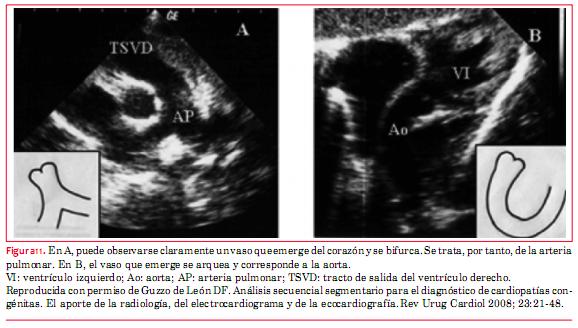

Respecto de los grandes vasos, la arteria pulmonar es el vaso que se bifurca(16) (figuras 11 y 12). Esta anomalía puede llegar a la vida adulta sin tratamiento, excepto que se desarrolle incompetencia valvular tricuspídea (válvula AV sistémica) de grado severo, o bloqueo AV completo que requiera el implante de un marcapasos, y por eso tiene importancia su conocimiento para el ecocardiografista de adultos. Las anomalías asociadas más frecuentes son CIV y estenosis subpulmonar que se evalúan del mismo modo que cuando estas alteraciones se presentan de forma independiente. La incompetencia valvular sistémica (válvula tricúspide) se evalúa de modo equivalente a la insuficiencia valvular mitral.